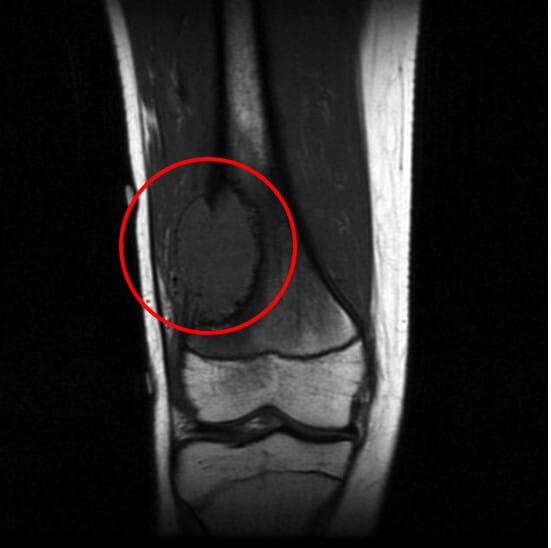

| MRI 소견 |

| T1에서는 종양 부위가 저신호, T2에서는 고신호를 보이며 명확한 종괴 형성 확인 |

| 골수 침범, 연부조직 확장, 주변 혈관 및 신경 구조와의 관계를 파악하기에 적절 |

| 수술 전 종양의 범위 및 수술 계획 수립에 필수 |